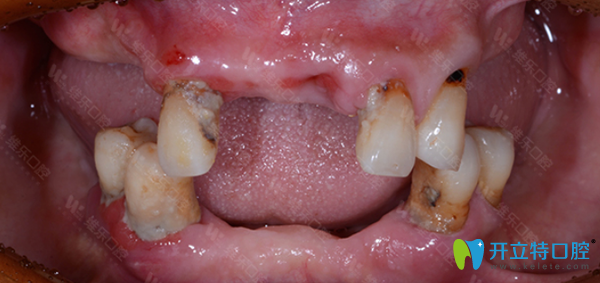

維樂(lè)口腔種牙前:

<!--<i data=20240703-sp></i>-->維樂(lè)口腔牙齒種植前

姓名:王先生 年齡:62歲

口腔問(wèn)題:牙齒脫落,牙槽骨脆弱,沒(méi)有牙營(yíng)養(yǎng)吸收低,整個(gè)人渾身無(wú)力。

主治醫(yī)師:翟建博 MAXI數(shù)字化疑難種植中心主任。

治療方案:全口種植。

種牙前,王大爺飽受缺牙帶來(lái)的種種折磨。經(jīng)翟建博主任仔細(xì)檢查后,建議采用數(shù)字化即刻負(fù)重種植牙技術(shù),來(lái)修復(fù)王大爺缺失的牙齒。